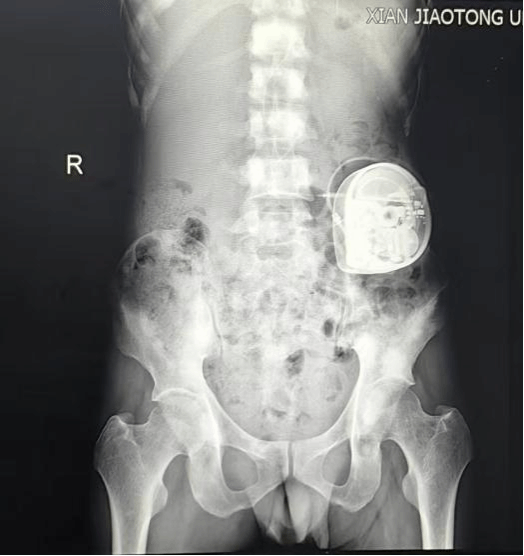

图2 镇痛泵容纳囊带制作

图4 X线透视确认镇痛泵位置良好